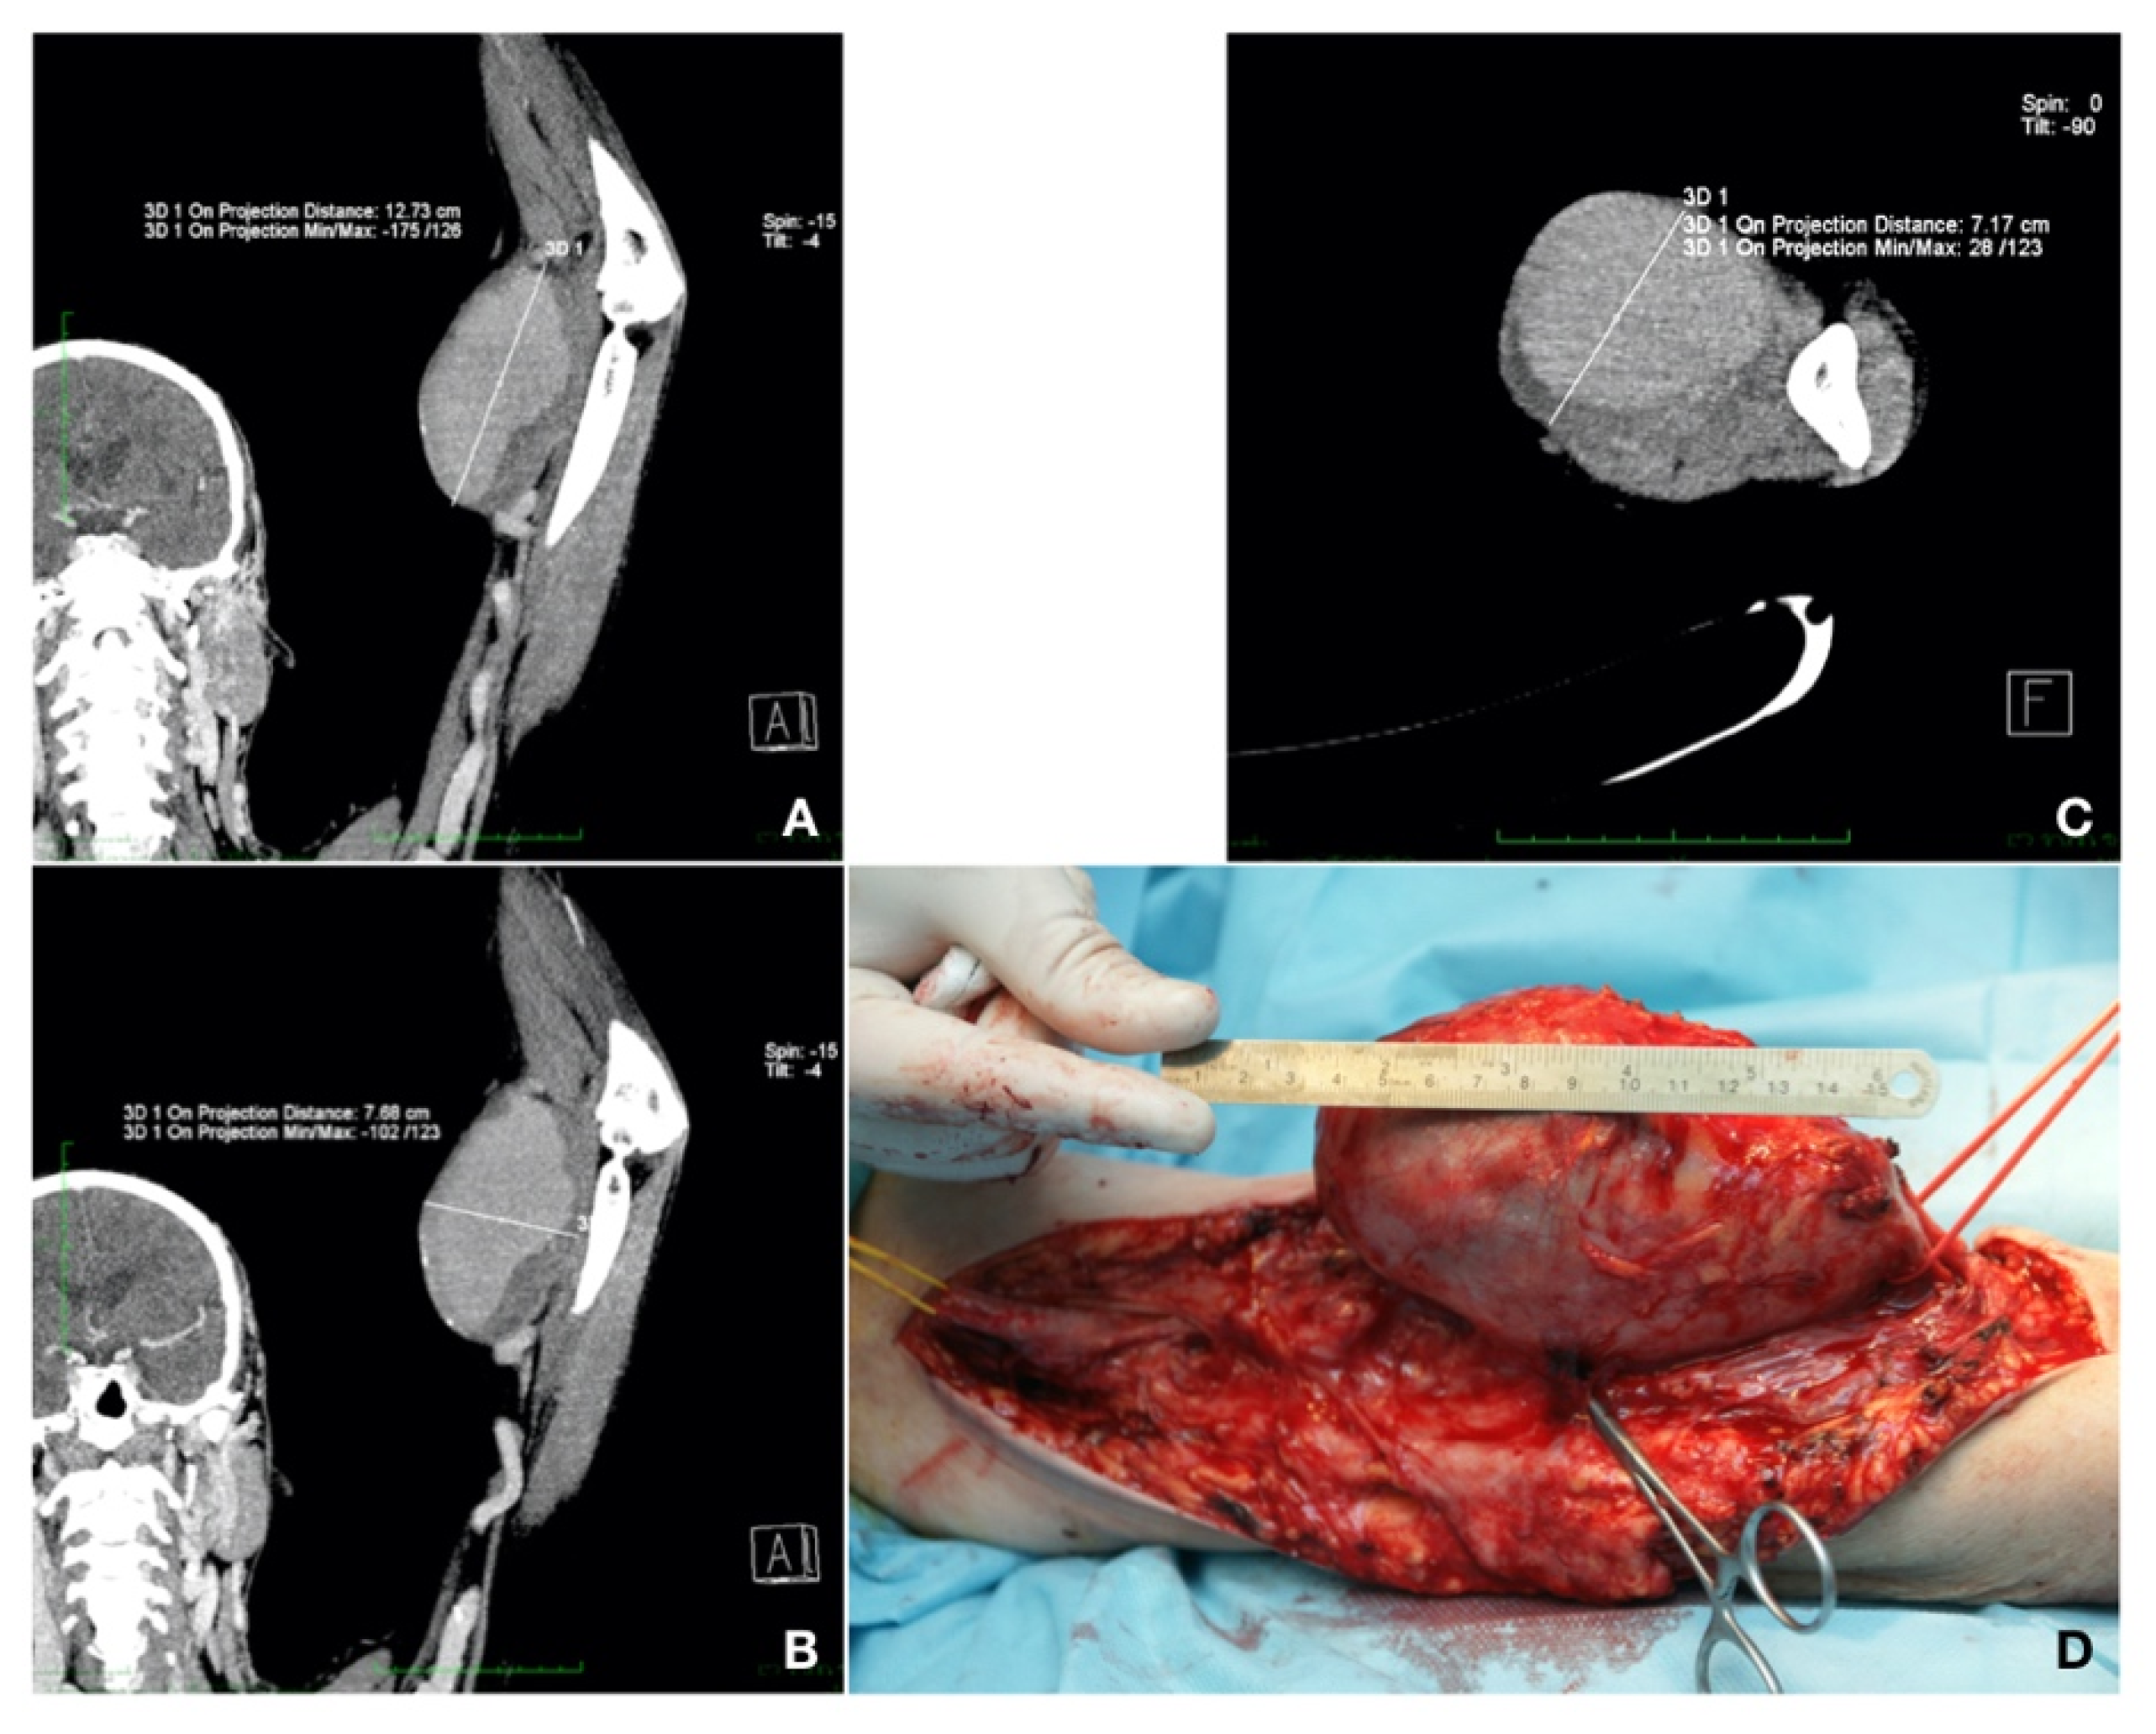

Case 1. A 59-year-old patient presented with a left brachial mass that had developed during the past 3 years. The patient also had type 2 diabetes mellitus, treated with diet, and dyslipidemia, treated with a statin. The mass was approximately 10 cm in size, pulsatile, but without any particular symptoms. The patient was known for chronic glomerulonephritis and chronic renal disease stage 5 KDIGO for 5 years. Three years previously, he had undergone live donor renal transplantation and, since then, he had been on immunosuppressive and steroid agents (fujimycin 0.5 mg, mycophenolic acid 2 × 180 mg, and prednisone 5 mg daily). After the RT, the AVF on the left side was closed. The patient was currently undergoing chronic RT rejection and hemodialysis three times per week. A CT-Angio of the left arm showed a brachial artery aneurysm of 12.73/7.68 cm, partially thrombosed. Aneurysm resection and vascular reconstruction with spatulated end-to-end anastomosis were performed [7]. The patient received preoperatively an adjusted dose of Ceftriaxone® (Antibiotice S.A., Iasi, Romania) at 1 g/dosage for infection prevention. An aneurysmectomy and reversed saphenous vein graft interposition, end-to-end anastomosis with 6.0 Prolene® (BBraun, Hessen, Germany) continuous sutures were performed under general anesthesia. The postoperative evolution was without complications (embolic, neurological, or surgical site bleeding or infection) and the patient was discharged 10 days after surgery (Figure 2).

Figure 2. (A,B) Longitudinal maximum intensity projection (MIP) section showing the aneurysm. (C) Transversal section. (D) Intraoperative image showing the dimensions of the aneurysm and proximal (yellow loop) and distal (red loop) ends of the vessels to be anastomosed with an inverted saphenous graft (personal collection).